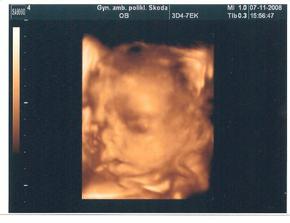

Tak grafy nevycházejí až tak úplně. Leontýnka je stále ještě na houbách a v bříšku nám roste Domino. Holt nevymřeme po meči - nebo jak se to říká :o)))

Jsme ve 30tt a kromě toho, že jsem už měsíc doma, se cítím v pořádku. Přesto se těším na každou kontrolu u paní doktorky. Už aby byli častěji.

Od Nového roku chodíme do poradny co týden. Už si užíváme poslouchání srdíčka na lehátku. První posíčci byli v noci z 11. na 12.ledna. Domino už má i svůj pokojíček :o)